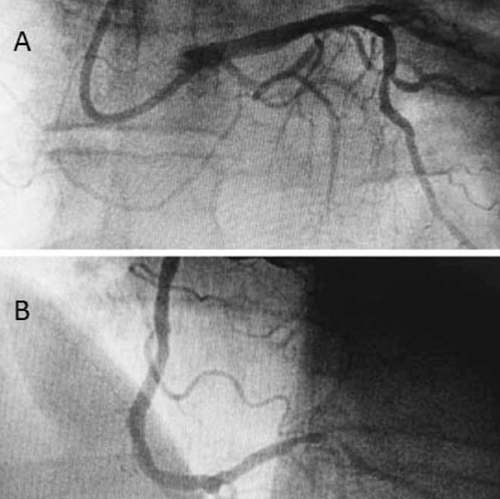

Se presenta una paciente de 61 años, hipertensa, diabética, extabaquista, portadora de sobrepeso, enfermedad pulmonar obstructiva crónica y cardiopatía isquémica, que cursó un síndrome coronario agudo (SCA) sin elevación del segmento ST en agosto de 2018. Se realizó angioplastia con implante de stent metálico sobre ramo marginal de arteria coronaria circunfleja (CX) sin complicaciones, presentando lesión residual moderada (50%) en arteria coronaria derecha (CD) dominante, en su sector distal (figura 1).

Figura 1: A) Lesión de ramo marginal de coronaria circunfleja. B) Lesión de coronaria derecha de 50%.